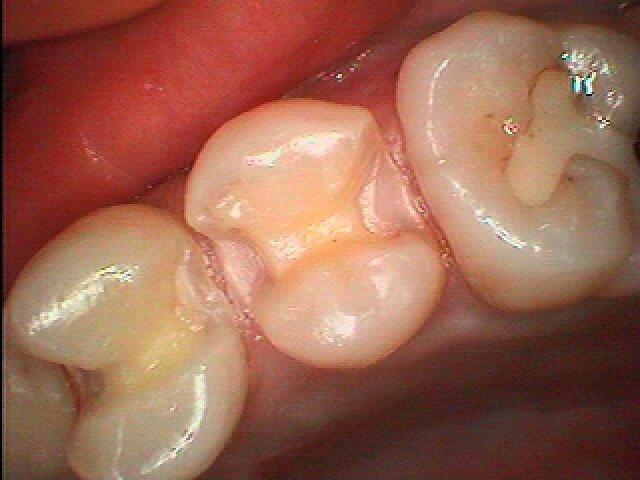

セラミックの作成はこんな感じになります。| |広島市安佐南区の歯科医院 セラミックの作成はこんな感じになります。 トップ お知らせ・ブログ セラミックの作成はこんな感じになります。 セラミックの作成はこんな感じになります。 Web診療予約 初めての方へ 選ばれ続ける理由 院内設備について 歯が痛いしみる一般歯科 歯がぐらぐらする歯周病 健康な歯を保ちたい予防歯科 子供の虫歯予防をしたい小児歯科 銀歯をセラミックに審美歯科 白い歯を目指しませんか?ホワイトニング 矯正専門医がいるので安心矯正歯科 抜けた歯を補いたいインプラント・入れ歯 医院案内 スタッフ紹介 メリィハウス歯科クリニックオフィシャルホームページ ラベンダー歯科クリニックオフィシャルホームページ お知らせ・ブログ ホーム 診療科目 一般歯科 歯周病治療 予防治療 小児歯科 審美治療 ホワイトニング 矯正歯科 入れ歯・インプラント マウスピース矯正 初めての方へ 院長・スタッフ 設備紹介 医院案内・アクセス メニューを閉じる